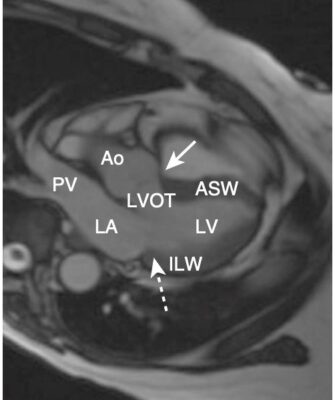

- Một trong những lợi ích của MRI là hình ảnh của nó có thể được hiển thị ở bất kỳ mặt phẳng nào. Bên cạnh các mặt phẳng cắt ngang (axial), đứng dọc (sagittal) và đứng bên (coronal, trán), có một số góc nhìn đặc hiệu thường được sử dụng trong MRI tim cho phép hình dung rõ nhất về tim. Chúng được gọi là trục dài cắt ngang (còn được gọi là mặt cắt bốn buồng), trục dài thẳng đứng, trục ngắn và mặt cắt ba buồng.

- Cấu trúc giải phẫu của tim trong các mặt phẳng cắt ngang, đứng dọc và trán giống như được thấy trên CT (Hình 16).

- Lát cắt ba buồng tương tự như lát cắt đứng bên và hiển thị gốc động mạch chủ và van động mạch chủ, đường ra thất trái, van hai lá, các thành trước vách và thành dưới bên của tâm thất trái (Hình 20).